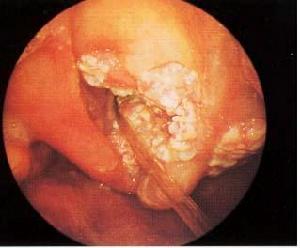

聲門下型喉癌1、聲門上型包括原發於聲帶以上部位的癌腫,如會厭、杓狀會厭襞、室帶和喉室等。此型癌腫分化較差,發展較快。由於該區淋巴管豐富,常易向頸深上組位於頸總動脈分叉處淋巴結轉移,早期症狀又覺喉部有異物感,咽部不適。以後癌腫表面潰爛時,則有咽喉著,可反射至耳部,甚至影響吞咽。晚期癌腫侵蝕血管後,則痰中帶血,常有臭痰路出;侵及聲帶時,則有聲嘶、呼吸困難等。

4、喉癌乳頭狀瘤 此病幼兒多發,成人可見,目前認為系病毒感染所致,常並發皮膚疣,男女無差別。主要表現為音啞,喉鏡見幼兒多在喉內各部發病,帶蒂,基底比較廣,呈現菜花狀。成人以單個帶蒂,常在聲帶發病,活動不受限,以男性為多,病變局限,病理檢查示重度不典型增生時,應徹底切除,以防惡變。